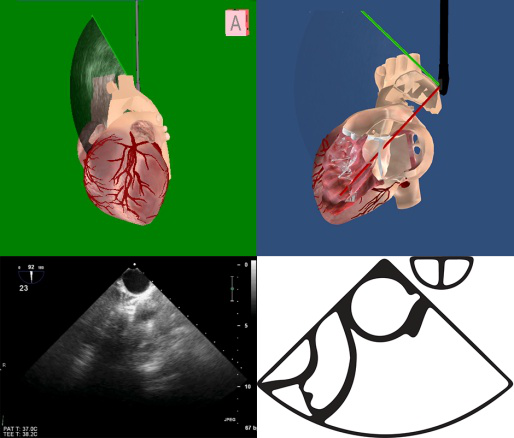

TEE切面与二尖瓣分区的对应关系可用于二尖瓣脱垂部位的判断,但要注意的是:一定要将2D或3D图像与二尖瓣模型对应起来,不理解切面和模型之间的空间关系,直接用文献上的分区对应实际的超声图像会导致定位不准和交流障碍(图11,12,13,14);另外,经胃底基底段短轴切面对诊断瓣叶裂和穿孔很有帮助,彩色多普勒可以提供有关反流束起源的信息(图14)。

图11四腔心切面显示二尖瓣后叶P2区脱垂

图14经胃底基底段短轴切面。示二尖瓣前后叶,P3区位于“扇形”的顶点